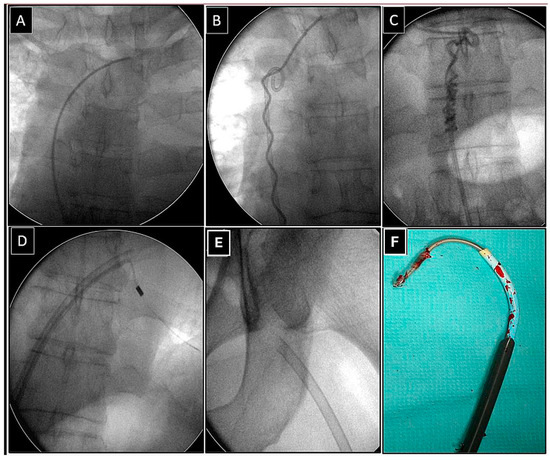

Extraction of Leads with Migrated Proximal Ends into the Cardiovascular Space

| Methods of removing fractured migrant leads | |||||

| Superior approach | 6 (15.39) | 3 (23.08) p = 0.832 | 3 (23.08) p = 0.832 | 5 (71.43) p = 0.007 | 17 (23.61) |

| Combined approach | 3 (7.69) | 3 (23.08) p = 0.316 | 1 (7.67) p = 0.548 | 1 (14.29) p = 0.874 | 8 (11.11) |

| Femoral approach | 29 (74.36) | 7 (53.85) p = 0.298 | 8 (61.54) p = 0.596 | 1 (14.29) p = 0.001 | 45 (62.50) |

| Main/final approach and tools | 45 (100.0) | Main/final approach and tools | 72 (100.0) |

| Lasso/basket inside 13 FWS, NE (dilatation) | 31 (68.89) | Lasso/basket 13, FWS, NE—femoral approach (dilatation) | 31 (43.06) |

| Lasso/basket inside another large sheath (polypropylene) (dilatation) | 5 (11.11) | ||

| Lasso/basket inside transseptal sheath (only pulling) | 9 (20.00) | Lasso/basket another large sheath—femoral (dilatation) | 5 (8.33) |

| Supporting tools and techniques | 45 (100.0) | Lasso/basket inside transseptal sheath—femoral approach (pulling only) | 9 (12.50) |

| Loop femoral approach (pulling, end release) | 35 (77.78) | Lasso/basket in CS sheath—superior approach (pulling only) | 1 (1.39) |

| Pig-tail + winding and shifting femoral (end release) | 7 (15.56) | Lasso/basket only—superior approach (pulling only) | 3 (4.17) |

| Pig-tail femoral (end orientation) | 3 (6.67) | Cardiac surgery | 2 (2.28) |